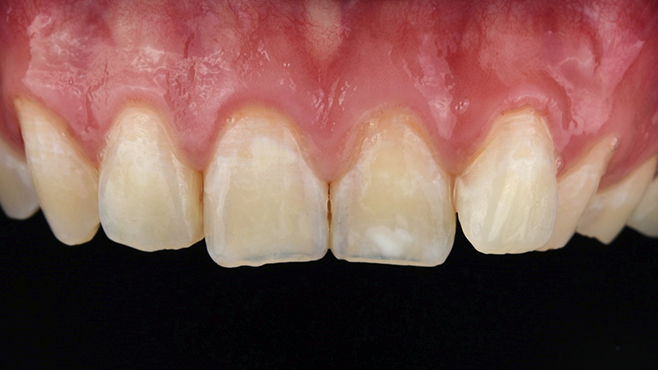

맞는 건 괜찮은데… 충치는 못 참겠습니다|20대 격투기 선수 치과 방문기